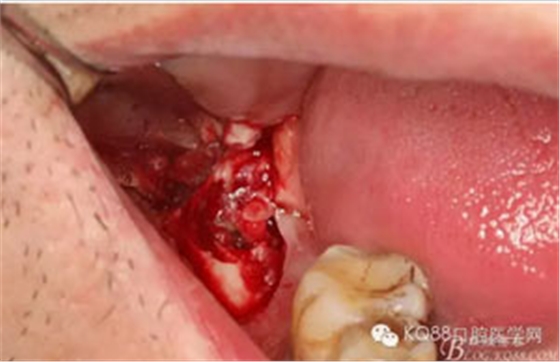

圖7.高速牙鉆去骨。逐漸可見48的牙冠

圖8.刮除牙冠表面的肉芽組織后,可見48 的牙冠